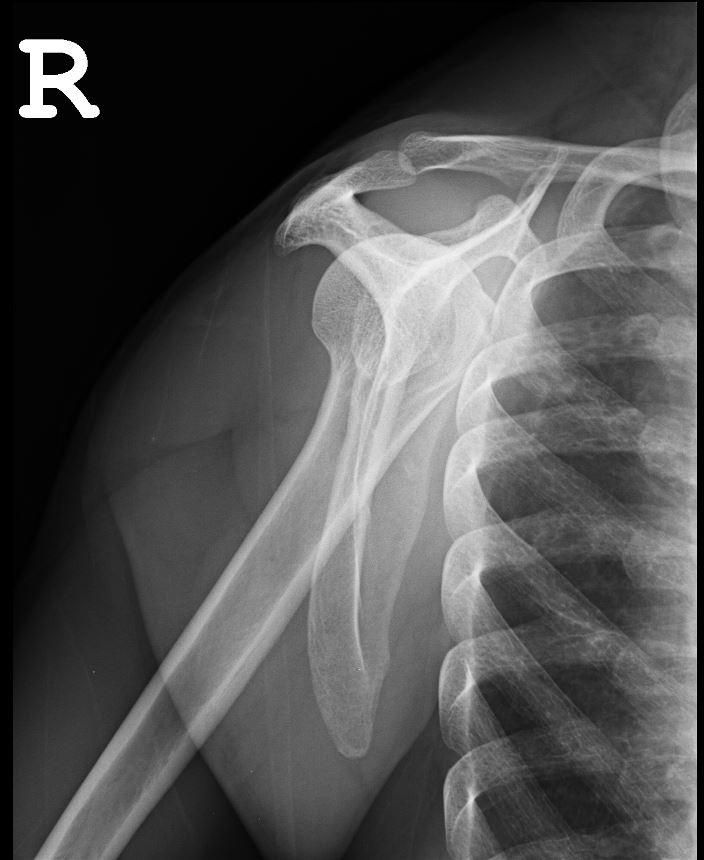

엑스레이 사진상 어깨탈구 소견이 있나요?

하기 사진은 그날 찍은 어깨 엑스레이입니다.

혹시 엑스레이상 어깨 탈골 소견이 있는지 궁금합니다.

사진상으로많은걸확인할수는없지만 엑스레이상에 큰 문제는보이지않는데요 소리가나는건 인대나 힘줄의마찰로인해서 생기는 소리일수있으니 좀더 정확한 진단을위해 MRI검사를 받아보시길 바랍니다

업로드 하신 어깨 엑스레이 사진에는 딱히 보이는 이상소견이 따로 있지 않습니다. 어깨 부위 탈구 소견이 관찰되지 않으며 정상 어깨 엑스레이 사진으로 보입니다. 어깨의 탈구가 있으면 심한 통증과 함께 움직임에 제한이 생기므로 단순히 소리가 나는 소견만으로는 탈구에 대해서 크게 걱정을 할 필요는 없습니다.

올려주신 어깨 엑스레이를 보면 뼈구조가 정상적으로 위치하고 있으며 명백한 탈구나 골절 소견은 보이지 않습니다. 어깨 관절은 비교적 안정적인 상태로 보입니다. 다만 어깨에서 뚝소리가 나는 것은 관절이나 힘줄, 인대가 움직이면서 나는 소리일 수 있으며 반드시 탈골을 의미하지는 않습니다! 통증이 없고 움직임도 정상적이라면 큰 문제 가능성은 낮습니다!안녕하세요. 김현태 물리치료사입니다.